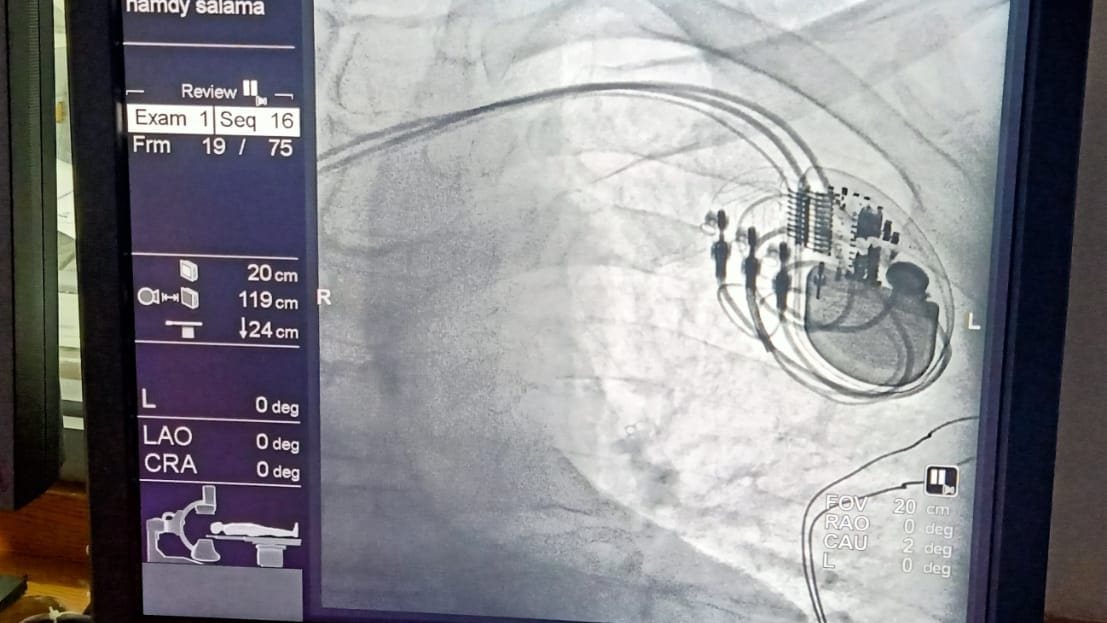

أنقذ فريق طبي بمركز أبحاث أمراض الكبد والقلب بمحافظة كفر الشيخ، حياة طفل يبلغ من العمر 5 سنوات، باستخراج جسم غريب «بطارية ساعة» كان قد ابتعلها أثناء لهوه في منزله.

وكان الطفل قد وصل الطوارئ، بعد أن ابتلع جسم غريب «بطارية ساعة» أثناء لهوه بمنزله، وجرى إنقاذه على الفور داخل وحدة المناظير نظراً لخطورة الجسم الغريب الذي يعمل على تهتكات وثقب المرئ.